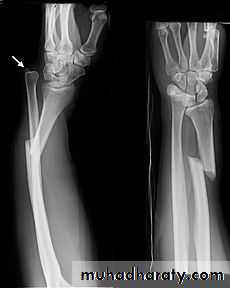

Upper limb

Fall on out stretched hand

xray

Possible complications

complication